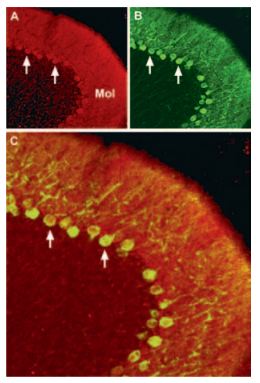

Immunohistochemical staining of CaV2.1 channel with Anti-CACNA1A (CaV2.1) Antibody (#ACC-001) (1:100) in mouse cerebellum. (A) CaV2.1 channel (red) appears in Purkinje cells (horizontal arrows) and is distributed diffusely in the molecular layer (Mol) including in astrocytic fibers (vertical arrows). (B) staining of astrocytic fibers with glial fibrillary acidic protein (blue – originally green digitally edited to blue) in the section demonstrates the location of astrocytic fibers in the molecular layer. (C) Confocal merge CaV2.1 and GFAP.